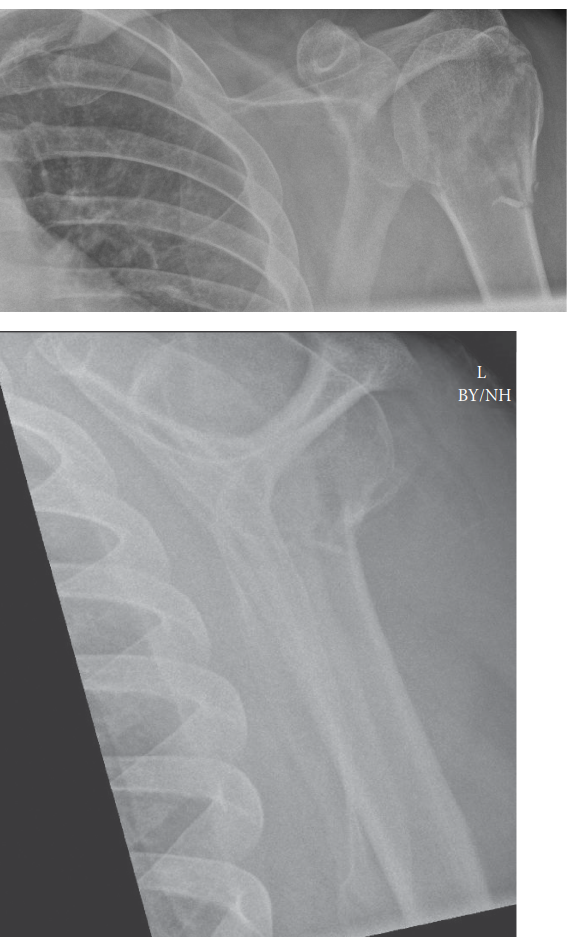

An 80-year-old woman attends the fracture clinic after stumbling and hitting her shoulder Against a banister.…